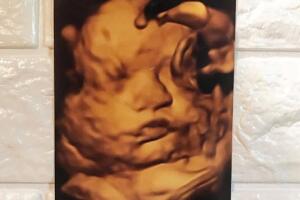

La noche del 24 de enero de 2019 El Dasa anunció en Instagram que se convertiría en padre. Un día después en el show Despierta América, reveló al lado de su pareja Jennifer Loya estaba esperando a una niña que llevaría el nombre de Daryana Marie.

El mánager del cantante de regional mexicano confirmó la noticia a Univision Entretenimiento, detallando que Daryana Marie nació a las 3:30 de la mañana hora del oeste de EEUU en la ciudad de Las Vegas, Nevada. El representante agregó que "nació muy bien y El Dasa y Jennifer están muy contentos".